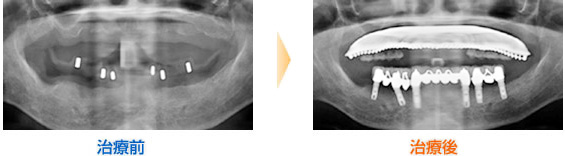

■70歳女性

インプラントを13本埋入